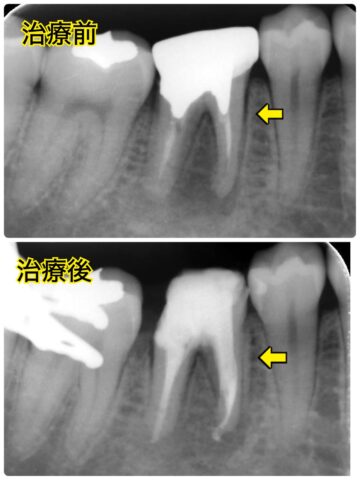

抜歯と言われ大きな根尖病変がある右下の感染根管治療を行いました。

そして、最初に治療した右下奥の歯は矯正用仮歯からオールセラミックスへ✨

オールセラミックスを入れる前のCTで、溶けてしまっていた骨がしっかりと回復しているのが分かります😊

↓オールセラミックスを入れた後のレントゲン写真での比較です。